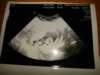

Hej Kochane. Ja dopiero do domu wróciłam. Tez dzisiaj pierwszy raz usłyszałam serduszko i łezka poleciala. Maluszek rośnie i wierzgal na usg jak szalony. Moja gin próbowała zrobić w 3d jakieś ładne zdjęcie ale nie dalo rady. Mam już kartę ciąży z czego się ciesze niesamowicie. Musze tylko cytologie i mocz zrobić z badań.

A mi termin porodu zmienił się o dzień do przodu wiec wychodzi 4 czerwca.